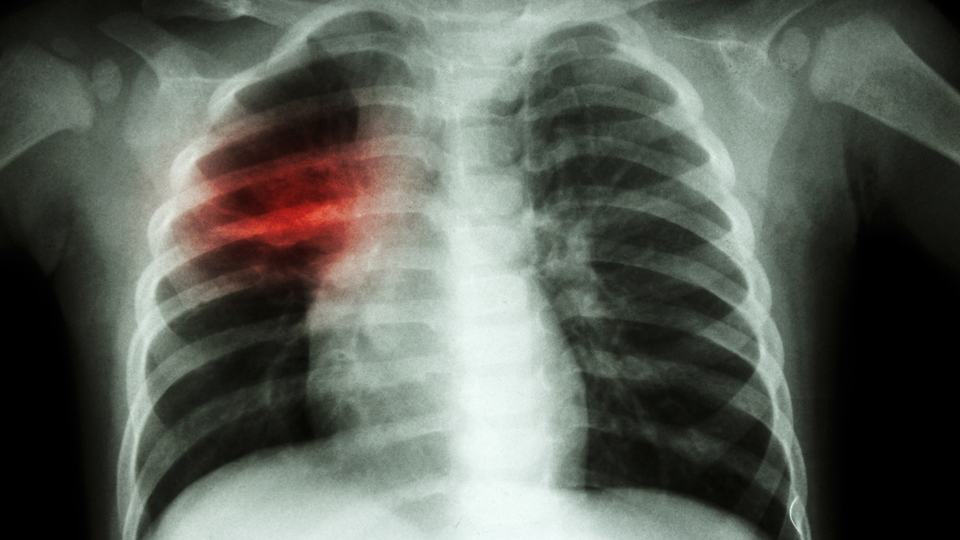

Prof. Dr. Atilla Eroğlu, akciğer kanserine ilişkin, "Günde 150 kişi akciğer kanseri teşhisi alıyor. Bir Maraş depremi oldu. Maraş depreminde yaklaşık 60 bin canımızı kaybettik. Her yıl belki de Maraş depremi kadar kişi sadece akciğer kanserinden kaybediliyor. Biz aslında kanserden korkmuyoruz kanserin geç teşhis edilmesinden korkuyoruz" dedi

Prof. Dr. Atilla Eroğlu, dünyada en çok görülen kanser türünün akciğer kanseri olduğunu söyledi. Türkiye'de her yıl 45 bin kişinin akciğer kanseri teşhisi aldığını kaydeden Eroğlu, "Günde 150 kişi akciğer kanseri teşhisi alıyor. Bir Maraş depremi oldu. Maraş depreminde yaklaşık 60 bin canımızı kaybettik. Her yıl belki de Maraş depremi kadar kişi sadece akciğer kanserinden kaybediliyor. Biz aslında kanserden korkmuyoruz kanserin geç teşhis edilmesinden korkuyoruz. Erken tanı için özellikle 50 yaş üstü, günde bir paket sigara içen kişilerin yılda 1 defa düşük doz tomografilerle tarama yaptırmalarını öneriyoruz. Çünkü erken teşhis hayat kurtarır. Unutmayalım ki akciğer kanseri kader değildir. Önlenebilir bir kanser türüdür ve erken teşhis hayat kurtarır" diye konuştu. Tıp Fakültesi 1'nci sınıf öğrencisi Hamza Eren Akçay da erken tanının önemini anlattı.